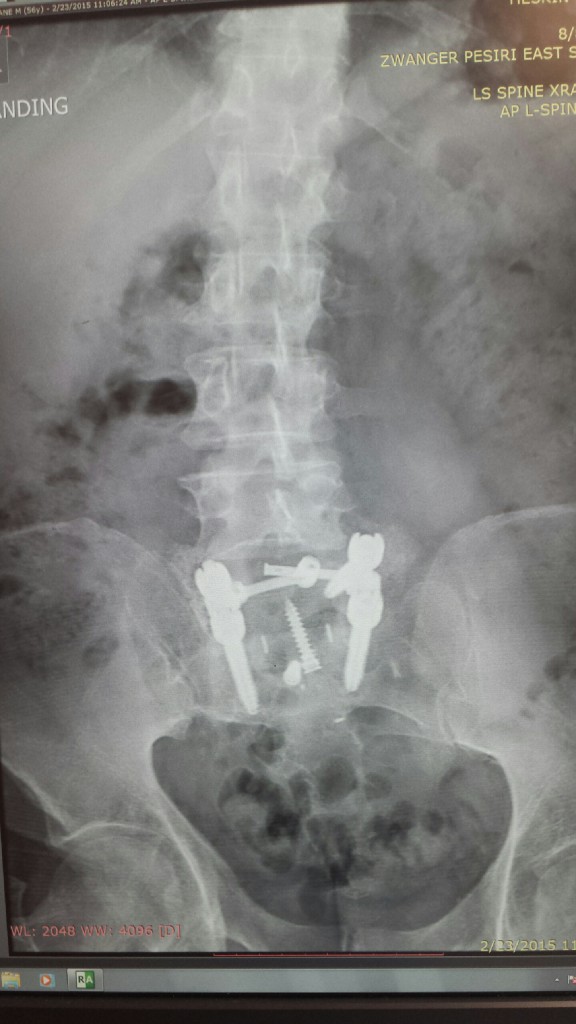

When I went to HSS for my surgery, I didn't know what to expect, but I think it was the best decision I ever made. I was in so much pain I could just about walk, I was told by Dr. Sama that he was going to anterior lumbar body fusion L5 S1 with posterior lumbar decompression, fusion, segmental spinal instrumentation L6 to S1 and I said "WOW! I don't have clue, but it takes away the pain and I can walk again lets do it." So January 12, 2015 was the date. My goal is to get back on the golf course play golf and to have many years of fun with my wife and family without PAIN. HSS has treated me with the care and respect that anyone going through what I have would need. It has been 7 weeks since my surgery and I am feeling better every day. The pain I had before the surgery is gone. I would just like to thank Dr. Sama and his staff for doing a great job. Also, all the people in the hospital, pain management, and any one that has helped when I had my surgery. I KNOW THAT WITH THE HELP OF HSS, I WILL BE BACK IN THE GAME ON THE GOLF COURSE. THANKS AGAIN.